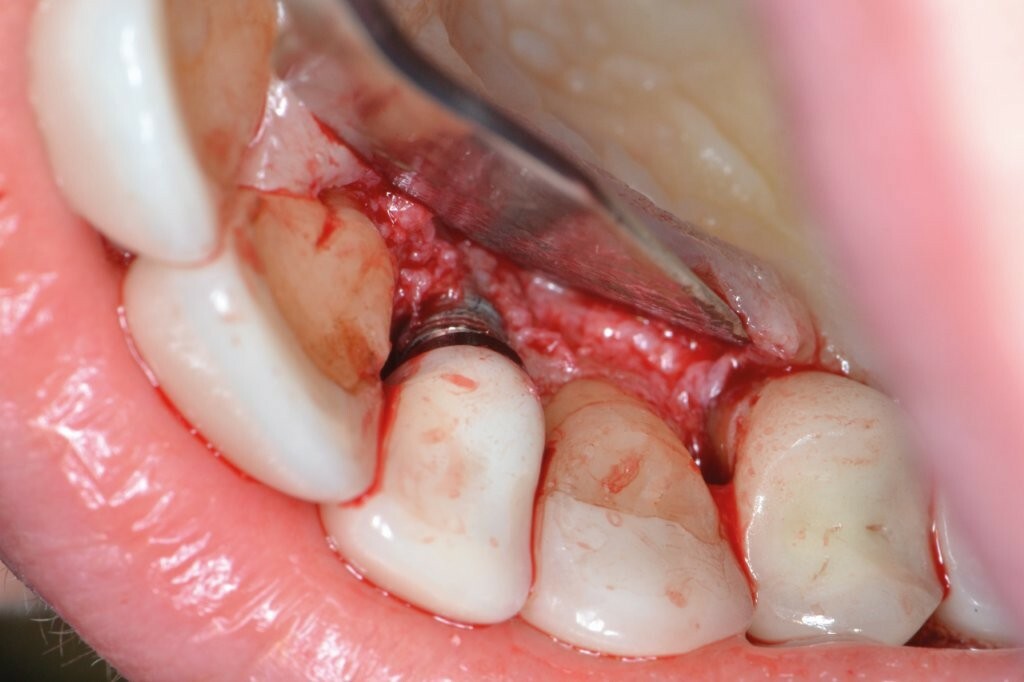

Im nachfolgenden Fallbericht wurde folgendes Protokoll befolgt: Der betroffene Bereich wird mittels Lappenchirurgie, gefolgt von einer gründlichen Kürettage des entzündeten Gewebes behandelt. Der Bereich wird mit sterilem Wasser besprüht. Dann erfolgt die Einlage von OXYSAFE-Gel – es wird für 5 Minuten auf die kontaminierte Implantatoberfläche aufgetragen. Der Bereich wird anschließend mit NaCl- und H2O2-Lösungen (10 Vol.) gespült. Eine zweite 5-minütige Anwendung von OXYSAFE-Gel wird durchgeführt. Der Bereich wird mit sterilem Wasser abgespült. In den periimplantären Knochendefekt wird sodann vorsichtig ein Knochenersatzmaterial eingebracht und mit einem Kollagenfleece abgedeckt. Anschließend wird der Lappen koronal vernäht.

Ein Minilappen wurde sowohl bukkal als auch palatinal am Implantat unter Einbeziehung der beiden Nachbarzähne gebildet. Das entzündete Gewebe wurde kürettiert, wobei wir einen 3 mm großen horizontalen Defekt mit einem stärkeren Knochenverlust auf der bukkalen Seite feststellten. Gemäß des zuvor beschriebenen Protokolls erfolgten zwei aufeinanderfolgende 5-minütige Anwendungen von OXYSAFE-Gel. Der Defekt wurde vorsichtig mit einem Xenotransplantat aufgefüllt und mit einem Kollagenvlies abgedeckt, der Lappen anschließend koronal mit einer Kopfnaht vernäht.